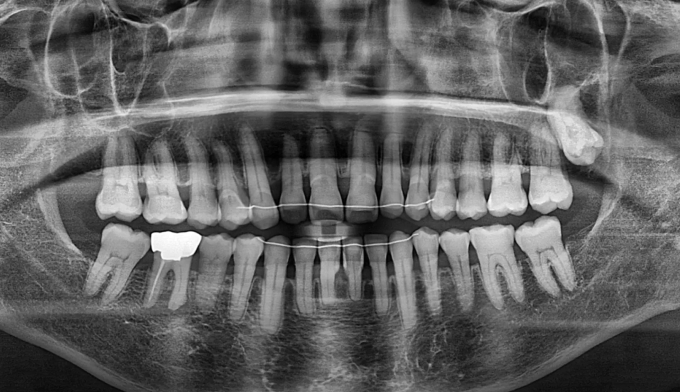

기존에 아래 앞니 사이 공간들에 레진이라는 치아색 나는 재료로 메워놓으셨던 분입니다. 나이가 들면서 잇몸이 약해지게되고 앞니가 점점 더 벌어질 수 있습니다.

타치과에서 다시 레진으로 공간을 없애려고 하였으나 더이상의 보철치료를 원하지 않으셔서, 기존에 존재하던 레진을 제거하면서 동시에 앞니 사이 공간을 교정치료를 이용해 닫아주기로 하였습니다.

기존에 앞니가 벌어지게 된 이유인 치주염을 치료하면서 동시에 앞니 공간을 교정을 통해 닫아줍니다.

총 교정기간은 9개월입니다.